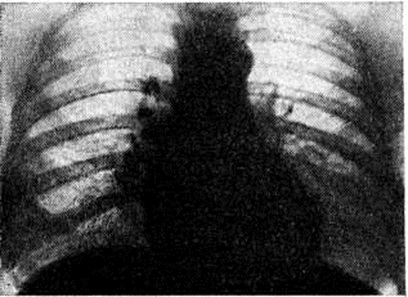

Рентгенологическая картина при Пневмокониозы зависит не только от степени фиброзных изменений в лёгких, но и от рентгеноконтрастности самой пыли, вдыхание которой вызывает развитие фиброза лёгочной ткани. При оценке рентгенологической картины принимается во внимание величина затемнений, их форма, контуры, плотность, площадь распространения. По характеру изменений различают узелковую, интерстициальную и узловую (конгломеративную) формы Пневмокониозы При интерстициальных Пневмокониозы на рентгенограммах лёгких (рисунок 2) преобладают интерстициальные изменения, при этом различают: s — тонкие линейные и сетчатые изменения, t — тяжистые затемнения неправильной формы, v — груботяжистые неправильной формы затемнения. Интерстициальный тип фиброза обычно соответствует I стадии Пневмокониозы, реже II стадии. При узелковых Пневмокониозы на рентгенограмме определяют мелкие округлые затемнения (узелки). Для обозначения их величины приняты латинские символы: р — узелки до 1,5 миллиметров в диаметре, q — от 1,5 до 3 миллиметров r — от 3 до 10 миллиметров. Узелки обычно имеют округлую форму, среднюю интенсивность тени и чёткие контуры. Располагаются они, как правило, диффузно, симметрично с обеих сторон. Независимо от их величины при I стадии пневмокониоза число узелков невелико, при II стадии отмечается умеренное их количество, при III стадии — узелки сливаются в конгломераты. Узелковый процесс, как правило, развивается на фоне интерстициального фиброза, выраженность которого особенно значительна при силикозе. Узловые (конгломеративные, иногда их называют опухолевидными) формы Пневмокониозы по величине узлов, выявляемых при рентгенографии, делят на мелкоузловые (символ А, диаметр узлов от 1 до 5 сантиметров), крупноузловые (символ В, диаметр узлов от 5 до 10 сантиметров при об щей площади узлов, не превышающей 1/3 лёгочного поля) и массивные (символ С, диаметр узлов более 10 сантиметров, а общая площадь их превышает 1/3 лёгочного поля). Узлы могут быть как в одном, так и в обоих лёгких, округлой или неправильной формы, контуры тени могут быть чёткими или размытыми. Узловые формы Пневмокониозы, как правило, соответствуют III стадии заболевания (рисунок 3).